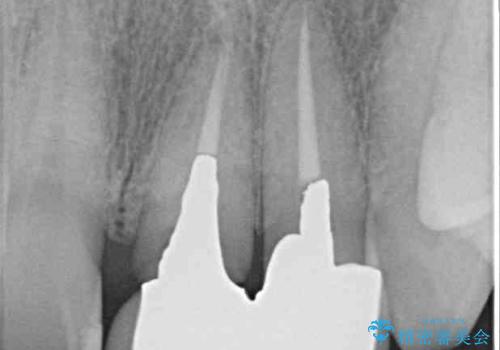

- 下顎前歯が抜けそうとのことで来院された患者様です。

初診の状態ではすぐにでも抜けそうな状態で、インプラントによる補綴治療を行うこととしました。

抜歯後にスペースができると恥ずかしいため、抜歯した歯を接着剤で固定した上で矯正治療を行い、その後インプラントやオールセラミッククラウンの装着を行うこととしました。